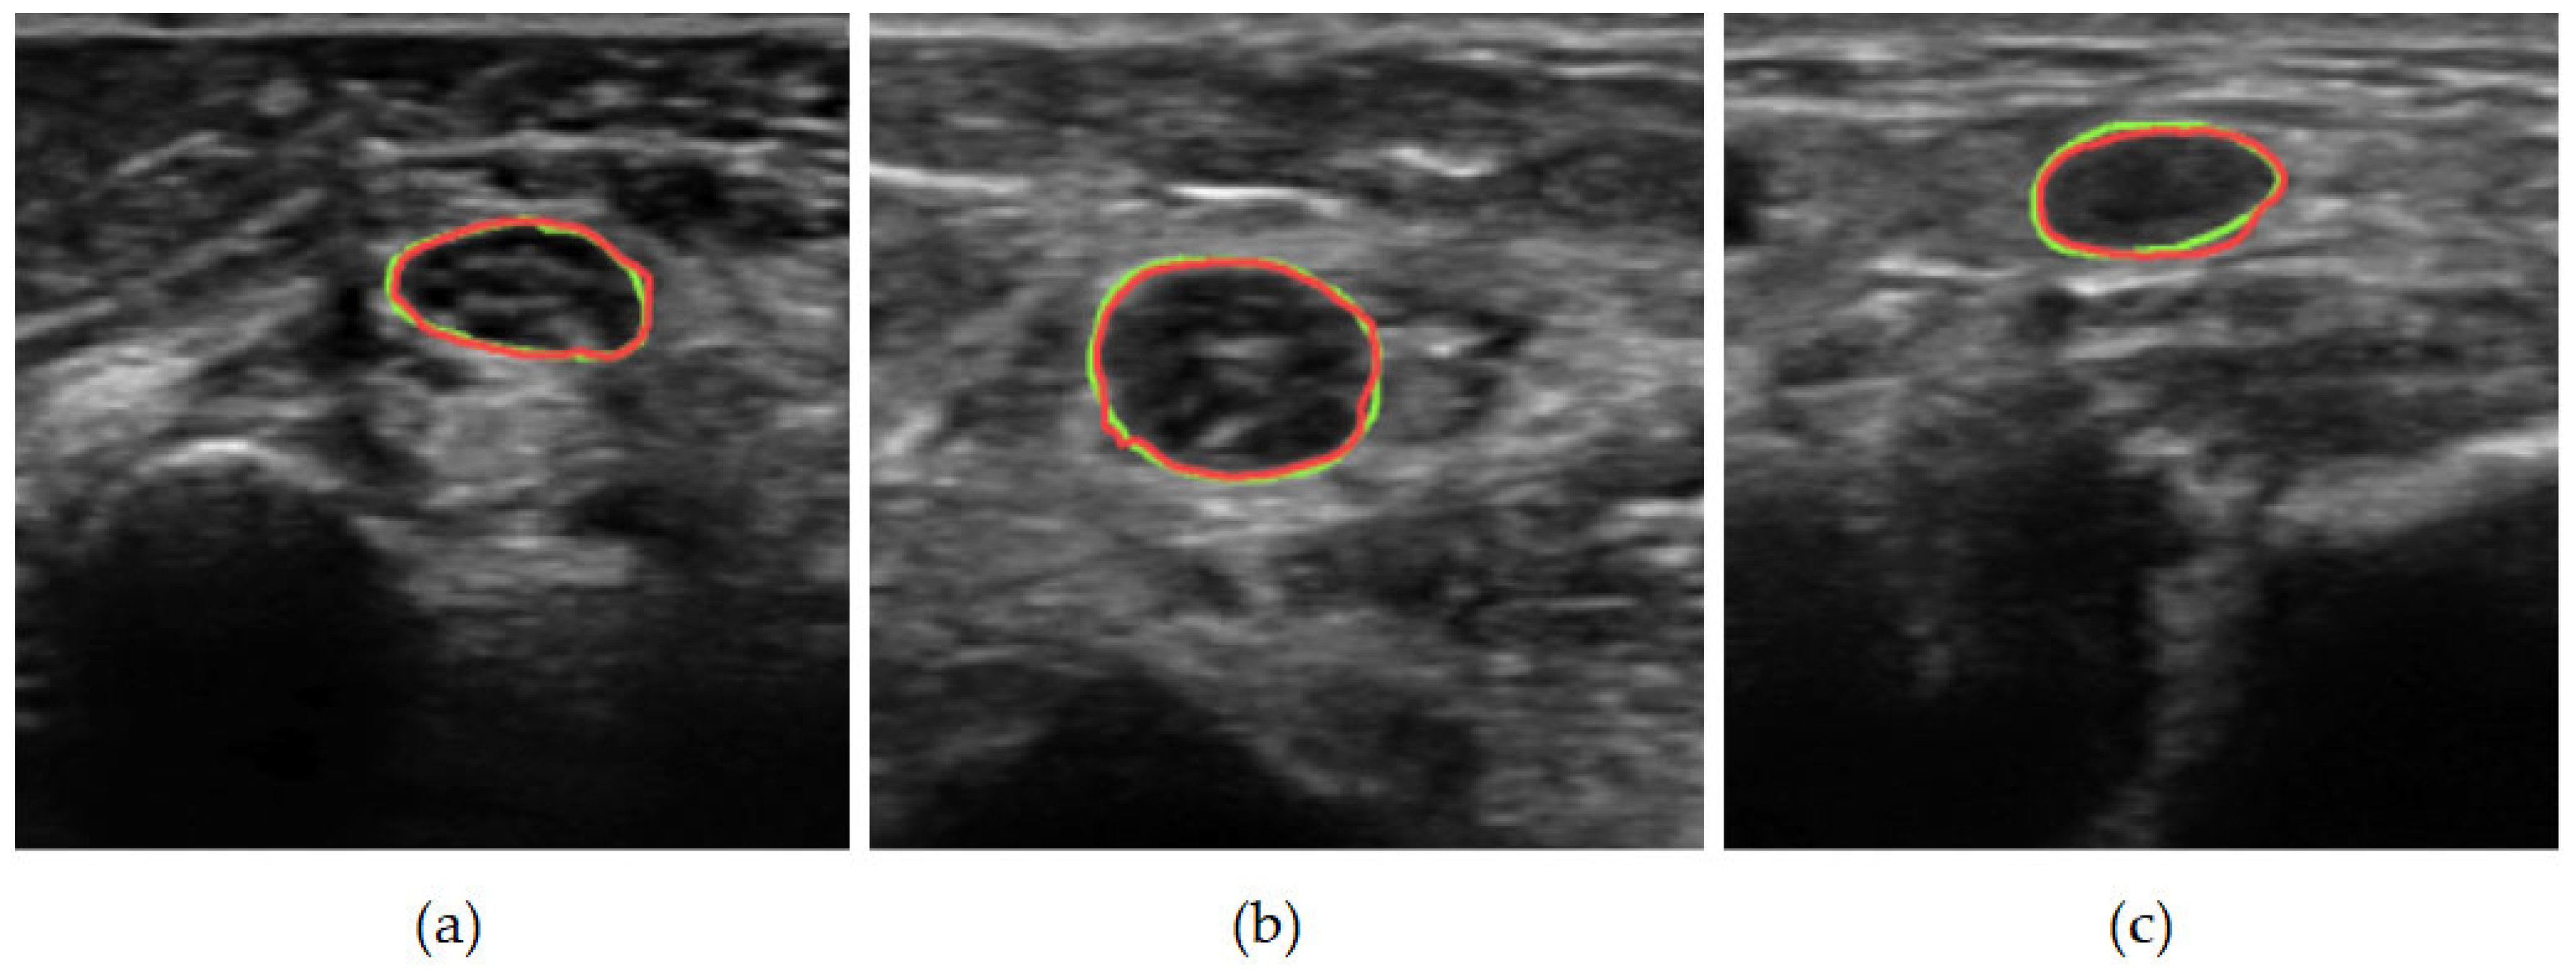

3.2. Qualitative